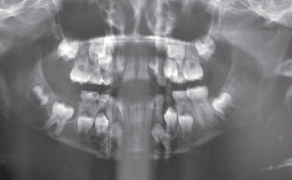

- Przypadek 1: Pacjent ogólnie zdrowy, lat 32, zgłosił się w celu wykonania badania stomatologicznego. Na wykonanym pantomogramie uwidoczniono rozległą torbiel okolicy zębów 45-47.

- Przypadek 2: Pacjent zgłosił się do Poradni w celu sanacji jamy ustnej. Badanie radiologiczne uwidoczniło zmianę o charakterze torbieli okolicy zęba 36. Stan po ekstrakcji zęba 37 rok wcześniej.

Streszczenie: W pracy przedstawiono dwa przypadki torbieli żuchwy o średnicy około 3 cm. Zastosowano leczenie jednoetapowe, podczas którego usunięto zmiany w całości wraz z przyczyną zębopochodną. Leczenie poprzez wyłuszczenie torbieli jest metodą z wyboru ze względu na zminimalizowanie ryzyka transformacji nowotworowej, możliwość oceny całego preparatu przez histopatologa oraz z powodu generowania najmniejszych niedogodności dla pacjenta. Diagnostyka z wykorzystaniem stożkowej tomografii komputerowej (CBCT) pozwoliła na ocenę wrażliwych struktur anatomicznych i zaplanowanie postępowania tak, aby zredukować ewentualne powikłania.

Summary: This paper presents two cases of mandible cysts with the diameter of approximately 3 cm. One-stage treatment was performed, during which the lesion was removed along with the affected teeth. Enucleation is a method of choice because it minimises the risk of cancer transformation, enables histopathological evaluation of the entire lesion and is the most comfortable for a patient. Diagnosis with the [...]